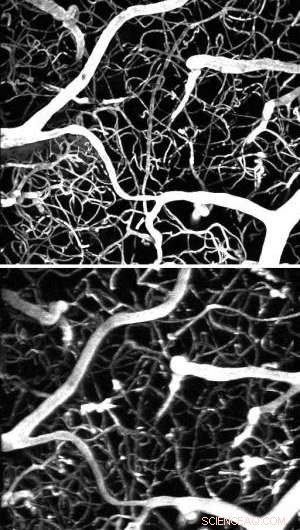

The same section of a mouse brain imaged with a femtosecond laser (above) and a much weaker laser but the new dye (below).

The researchers tested the efficacy of this approach on a mouse model. They started by injecting a conventional marker dye and using a femtosecond laser to map the vasculature of a section of the mouse's brain. They then switched to a laser that was a million times weaker and mapped the same region again, predictably producing no fluorescence. Finally, they kept the same weak laser but injected the dendrimer-coated nanoparticles, which allowed the researchers to produce the same imagery as in the first trial.

"This means we did the same experiment as the femtosecond laser but with one that costs hundreds of thousands of dollars less," Vinogradov said.

This experiment was the first demonstration of use of lanthanide nanoparticles in neuromiaging as well as the first example of two-photon in vivo microscopy with simple, inexpensive lasers.